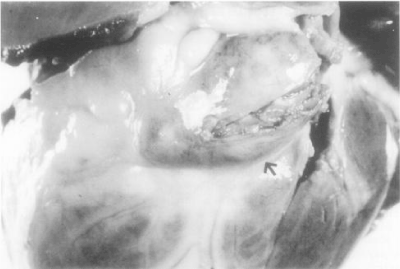

The pathophysiology of coronary artery aneurysms

Major pathological changes found in the coronary arteries are in the form of necrotizing arteritis, focal segmental destruction (Figure 1), aneurysms formation, (Figure 2), and thrombosis of a major coronary branch [43].

Figure 2. Frontal view of the heart showing a partially opened giant fusiform aneurysm of the left anterior descending coronary artery [arrow] in patient with KD. The lumen is filled with a thrombus [44].